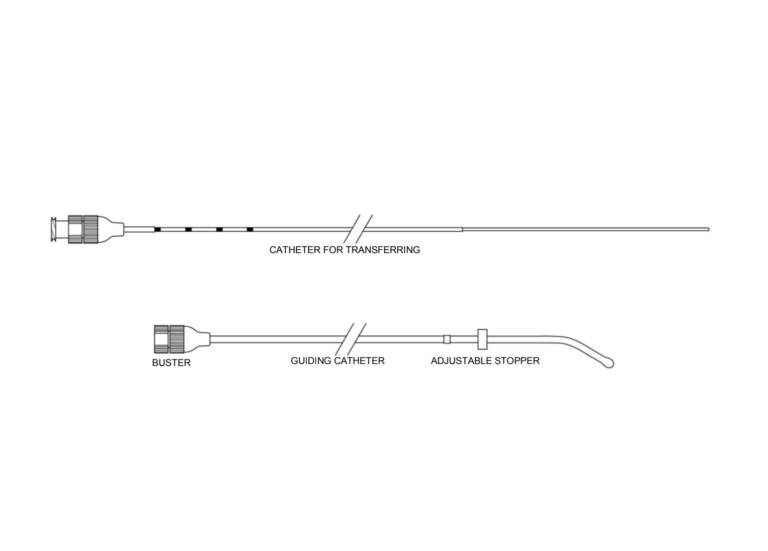

Guardia™ Access Embryo Transfer Catheter

DESCRIPTION:

Used to place in vitro fertilized (IVF) embryos into the uterine cavity.

- The guide catheter is curved to facilitate insertion.

- The guide catheter’s rounded bulb tip eases passage through the cervix.

- The transfer catheter is soft and flexible.The Microvol™ technology minimizes the volume of media that is required.

- The cervical stop comes set at 4 cm and can be adjusted to 5 cm. The catheters are packaged in separate sterile pouches.